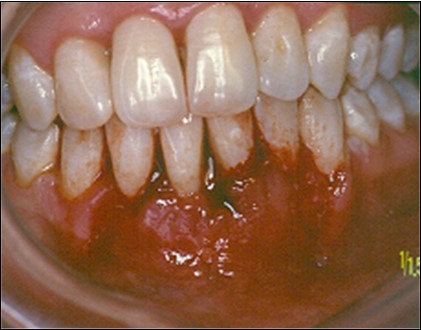

The patient under hard emotional stress that associated with bacterial plaque promoted ANUG with necrosis of alveolar bone and marginal gingival soft tissue in 31 and 41 (Figure 1). The patient was free of systemic disease and was not currently receiving any medication. Initial therapy was carried out using Er-YAG laser, to promote scaling and root planning and oral hygiene instruction. After initial therapy (Figure 2) the surgical method employed consists of the following steps as described by Langer and Langer5.